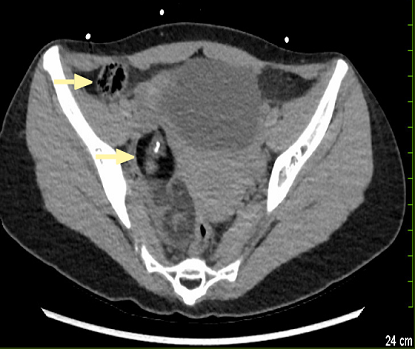

Adnexal torsion, including torsion of a normal or pathologic ovary, torsion of the fallopian tube, paratubal figure 2. Ct features of adnexal torsion. Malignancy in 16% of postmenopausal women vs.